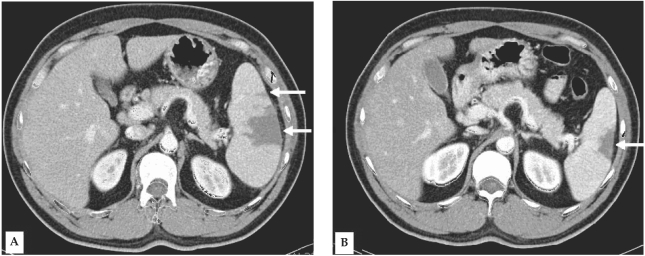

A 34-year-old man visited the Inha University Hospital in Incheon, Korea, complaining of a fever that had persisted for 5 days. Four days prior to the patient's visit, he had undergone ultrasonography at a nearby clinic, and was shown to be suffering from splenomegaly; the patient's spleen was approximately 14 cm long along the greatest axis. As malaria was not yet suspected in this case, medication was prescribed solely for symptomatic relief. At our outpatient department (OPD), fever and palpable splenomegaly were detected, and trophozoites and schizonts of P. vivax were detected at a density of 1.875 × 109/L. A blood examination revealed the following: hemoglobin level, 9.8 mM/L; white blood cell count, 3.8 × 109/L; and platelet count, 47 × 109/L. Serum aspartate aminotransferase, alanine aminotransferase, and bilirubin levels were as follows: 1.77 mM/L, 2.42 mM/L, and 28.9 µM/L, respectively. The patient was prescribed a course of chloroquine (25 mg/kg over 48 hr) and was instructed to take primaquine after the fever had subsided. Six days later, the patient made another visit to the OPD, due to pain in the left upper abdomen, accompanied by pain in the left shoulder. The patient was afebrile, but continued to exhibit palpable splenomegaly. Upon admission, computed tomography (CT) of the abdomen revealed findings consistent with splenic infarction, i.e., multiple areas of low attenuated density in the enlarged spleen (Fig. 1A). Over the 3 days of hospitalization, the patient's other vital signs remained stable. No malarial trophozoites were observed on the blood smear. The patient's hemoglobin level, white blood cell count, and platelet count were 8.0 mM/L, 10 × 109/L, and 336 × 109/L, respectively. Liver function tests and tests for markers of hypercoagulable conditions, such as protein C or antithrombin III, were all normal. Upon discharge, the patient was prescribed a 14-day regimen of primaquine (15 mg/day), coupled with an analgesic that promptly relieved the patient's abdominal pain. 10 weeks later, the patient evidenced no symptoms consistent with splenic infarction, and a follow-up abdominal CT revealed partial resolution of the splenic infarction (Fig. 1B).